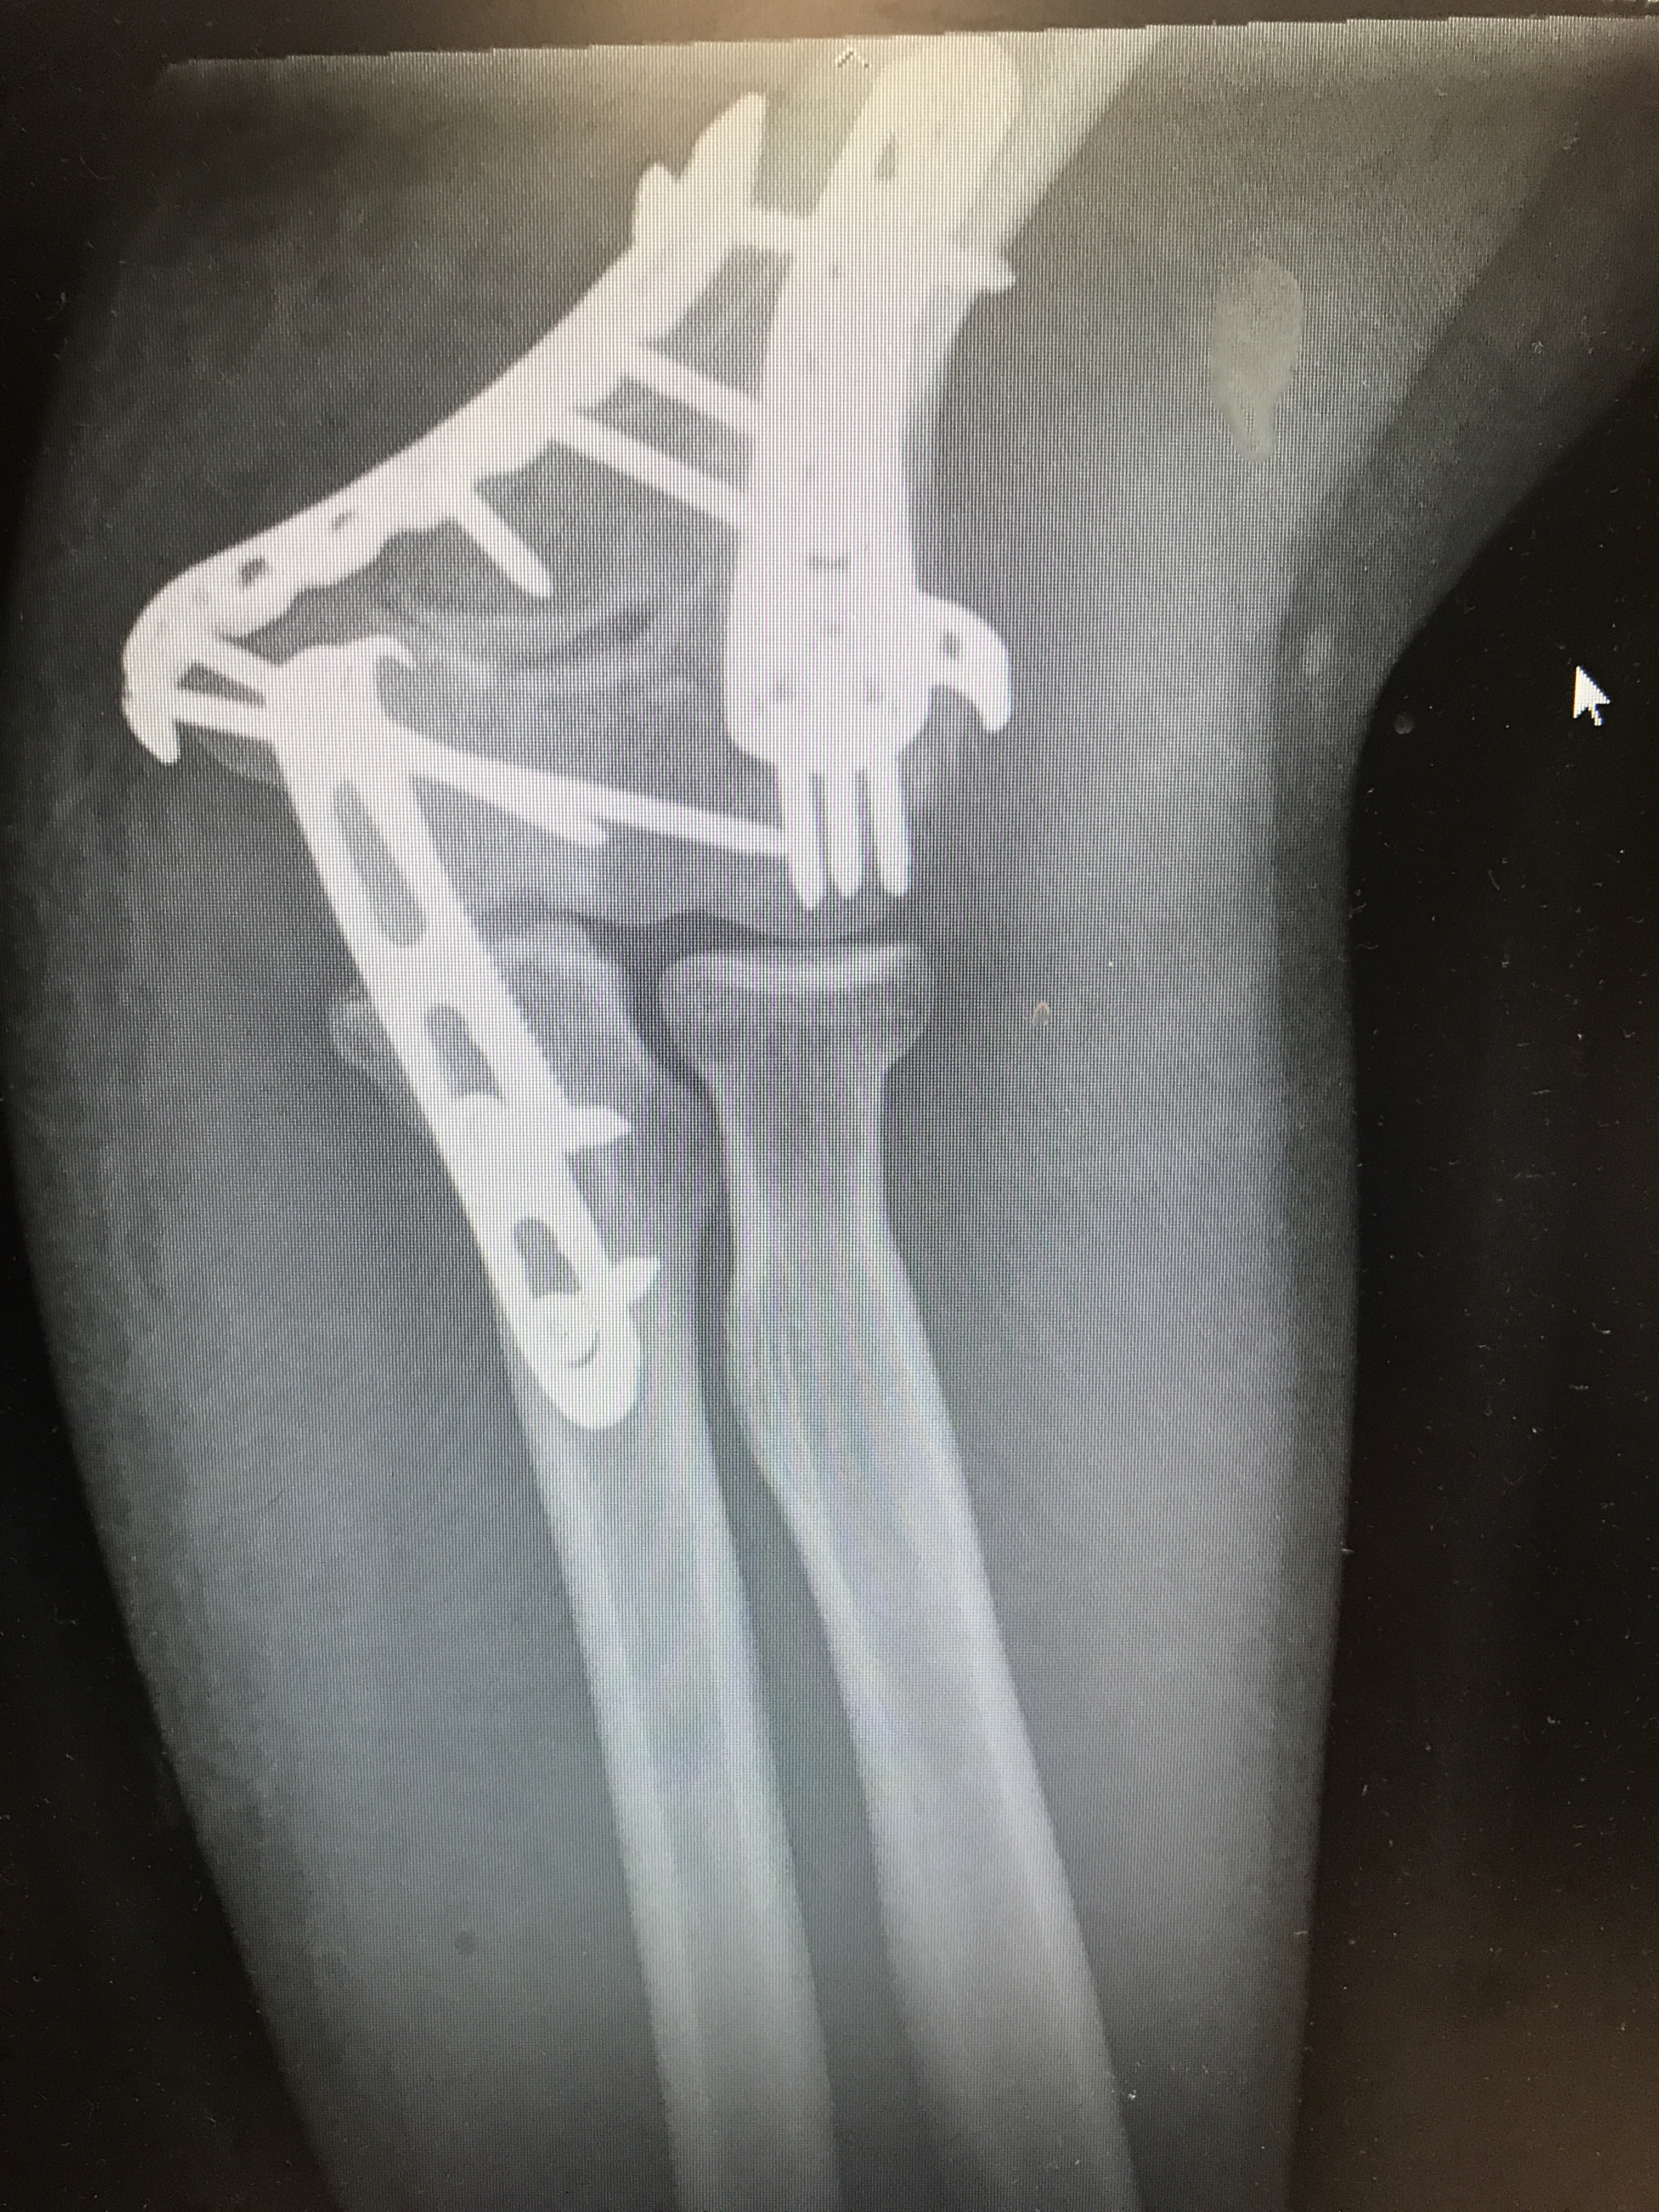

When the day finally came for the operation, you really stepped up. As soon as I woke you were there holding my hand, wearing your most serious outfit yet – you called it Morphine. Every five minutes I would give my hand a squeeze and feel you there supporting me. Helping me so that even after the surgeon had cut through my skin and drilled metal into my bones, I could still function without pain. I could eat, drink, use the bathroom, walk around. The surgeon told me I would have to lean on you for a while, and he was right, I could have never have gotten through it without you.